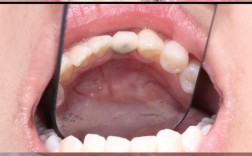

- 洁治(洗牙): 去除牙菌斑和牙结石。

- 龈下刮治和根面平整: 清洁牙龈下方的牙结石和病变牙根表面。

- 牙周手术: 对于中重度牙周炎,可能需要翻瓣术等手术来彻底清洁深部病变组织。